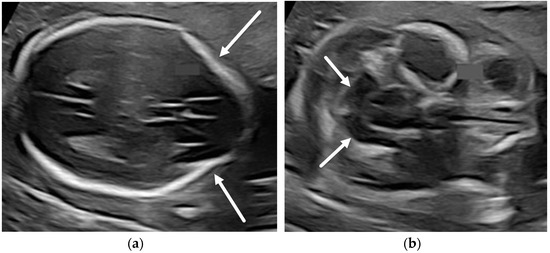

4.2. Corpus Callosum Anomalies

- Paladini, D.; Pastore, G.; Cavallaro, A.; Massaro, M.; Nappi, C. Agenesis of the fetal corpus callosum: Sonographic signs change with advancing gestational age. Ultrasound Obstet. Gynecol. 2013, 42, 687–690. [Google Scholar] [CrossRef] [PubMed]

- Tang, P.H.; Bartha, A.I.; Norton, M.E.; Barkovich, A.J.; Sherr, E.H.; Glenn, O.A. Agenesis of the corpus callosum: An MR imaging analysis of associated abnormalities in the fetus. Am. J. Neuroradiol. 2009, 30, 257–263. [Google Scholar] [CrossRef] [PubMed] [Green Version]